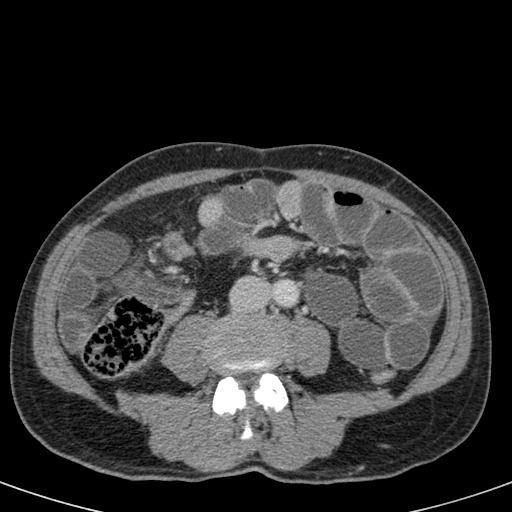

Tắc ruột dạng quai kín với các quai ruột giãn xếp theo hình nan hoa. Có dày thành ruột và phù nề mạc treo gợi ý thiếu máu cục bộ

Một hình ảnh quan trọng khác của tắc ruột dạng quai kín là các quai ruột non giãn xếp theo hình nan hoa với các mạch máu mạc treo hội tụ về một điểm trung tâm.

Hình ảnh này hầu như luôn do xoắn ruột non gây ra.

Các dấu hiệu thiếu máu cục bộ trong tắc ruột dạng quai kín tương tự như ở bệnh nhân thiếu máu mạc treo do các nguyên nhân khác:

- dày thành ruột

- phù nề mạc treo

- cổ trướng

- sự ngấm thuốc của thành ruột trong thiếu máu cục bộ có thể bình thường, tăng hoặc giảm.